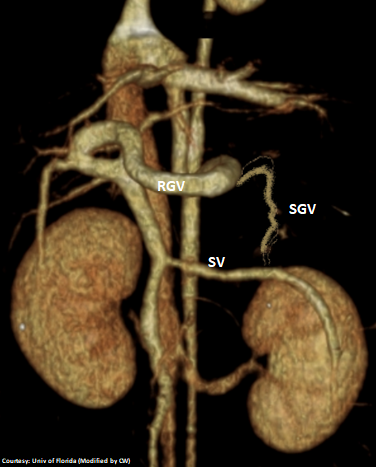

Left Gastric – Left Hepatic Vein shunt with Right Gastric Vein Contribution

Courtesy: Nihon Univ